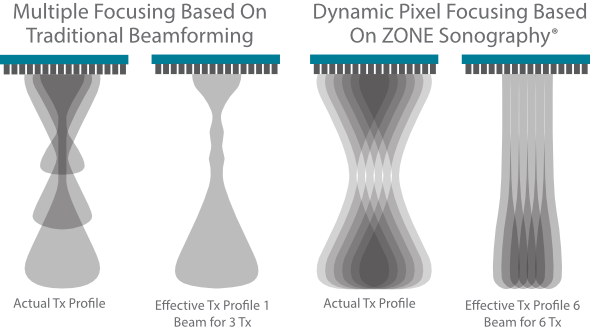

Mindray? ??? ??? ?? ??? ???? ??? ?? ??? ??? ????? ??? ????. ?? ???? ZONE Sonography? ??? ???? ?? Resona 7? ??? ZST+ ???? ?? ?? ? ?? ??? ????? ?? ??? ??? ??? ? ?? ????.